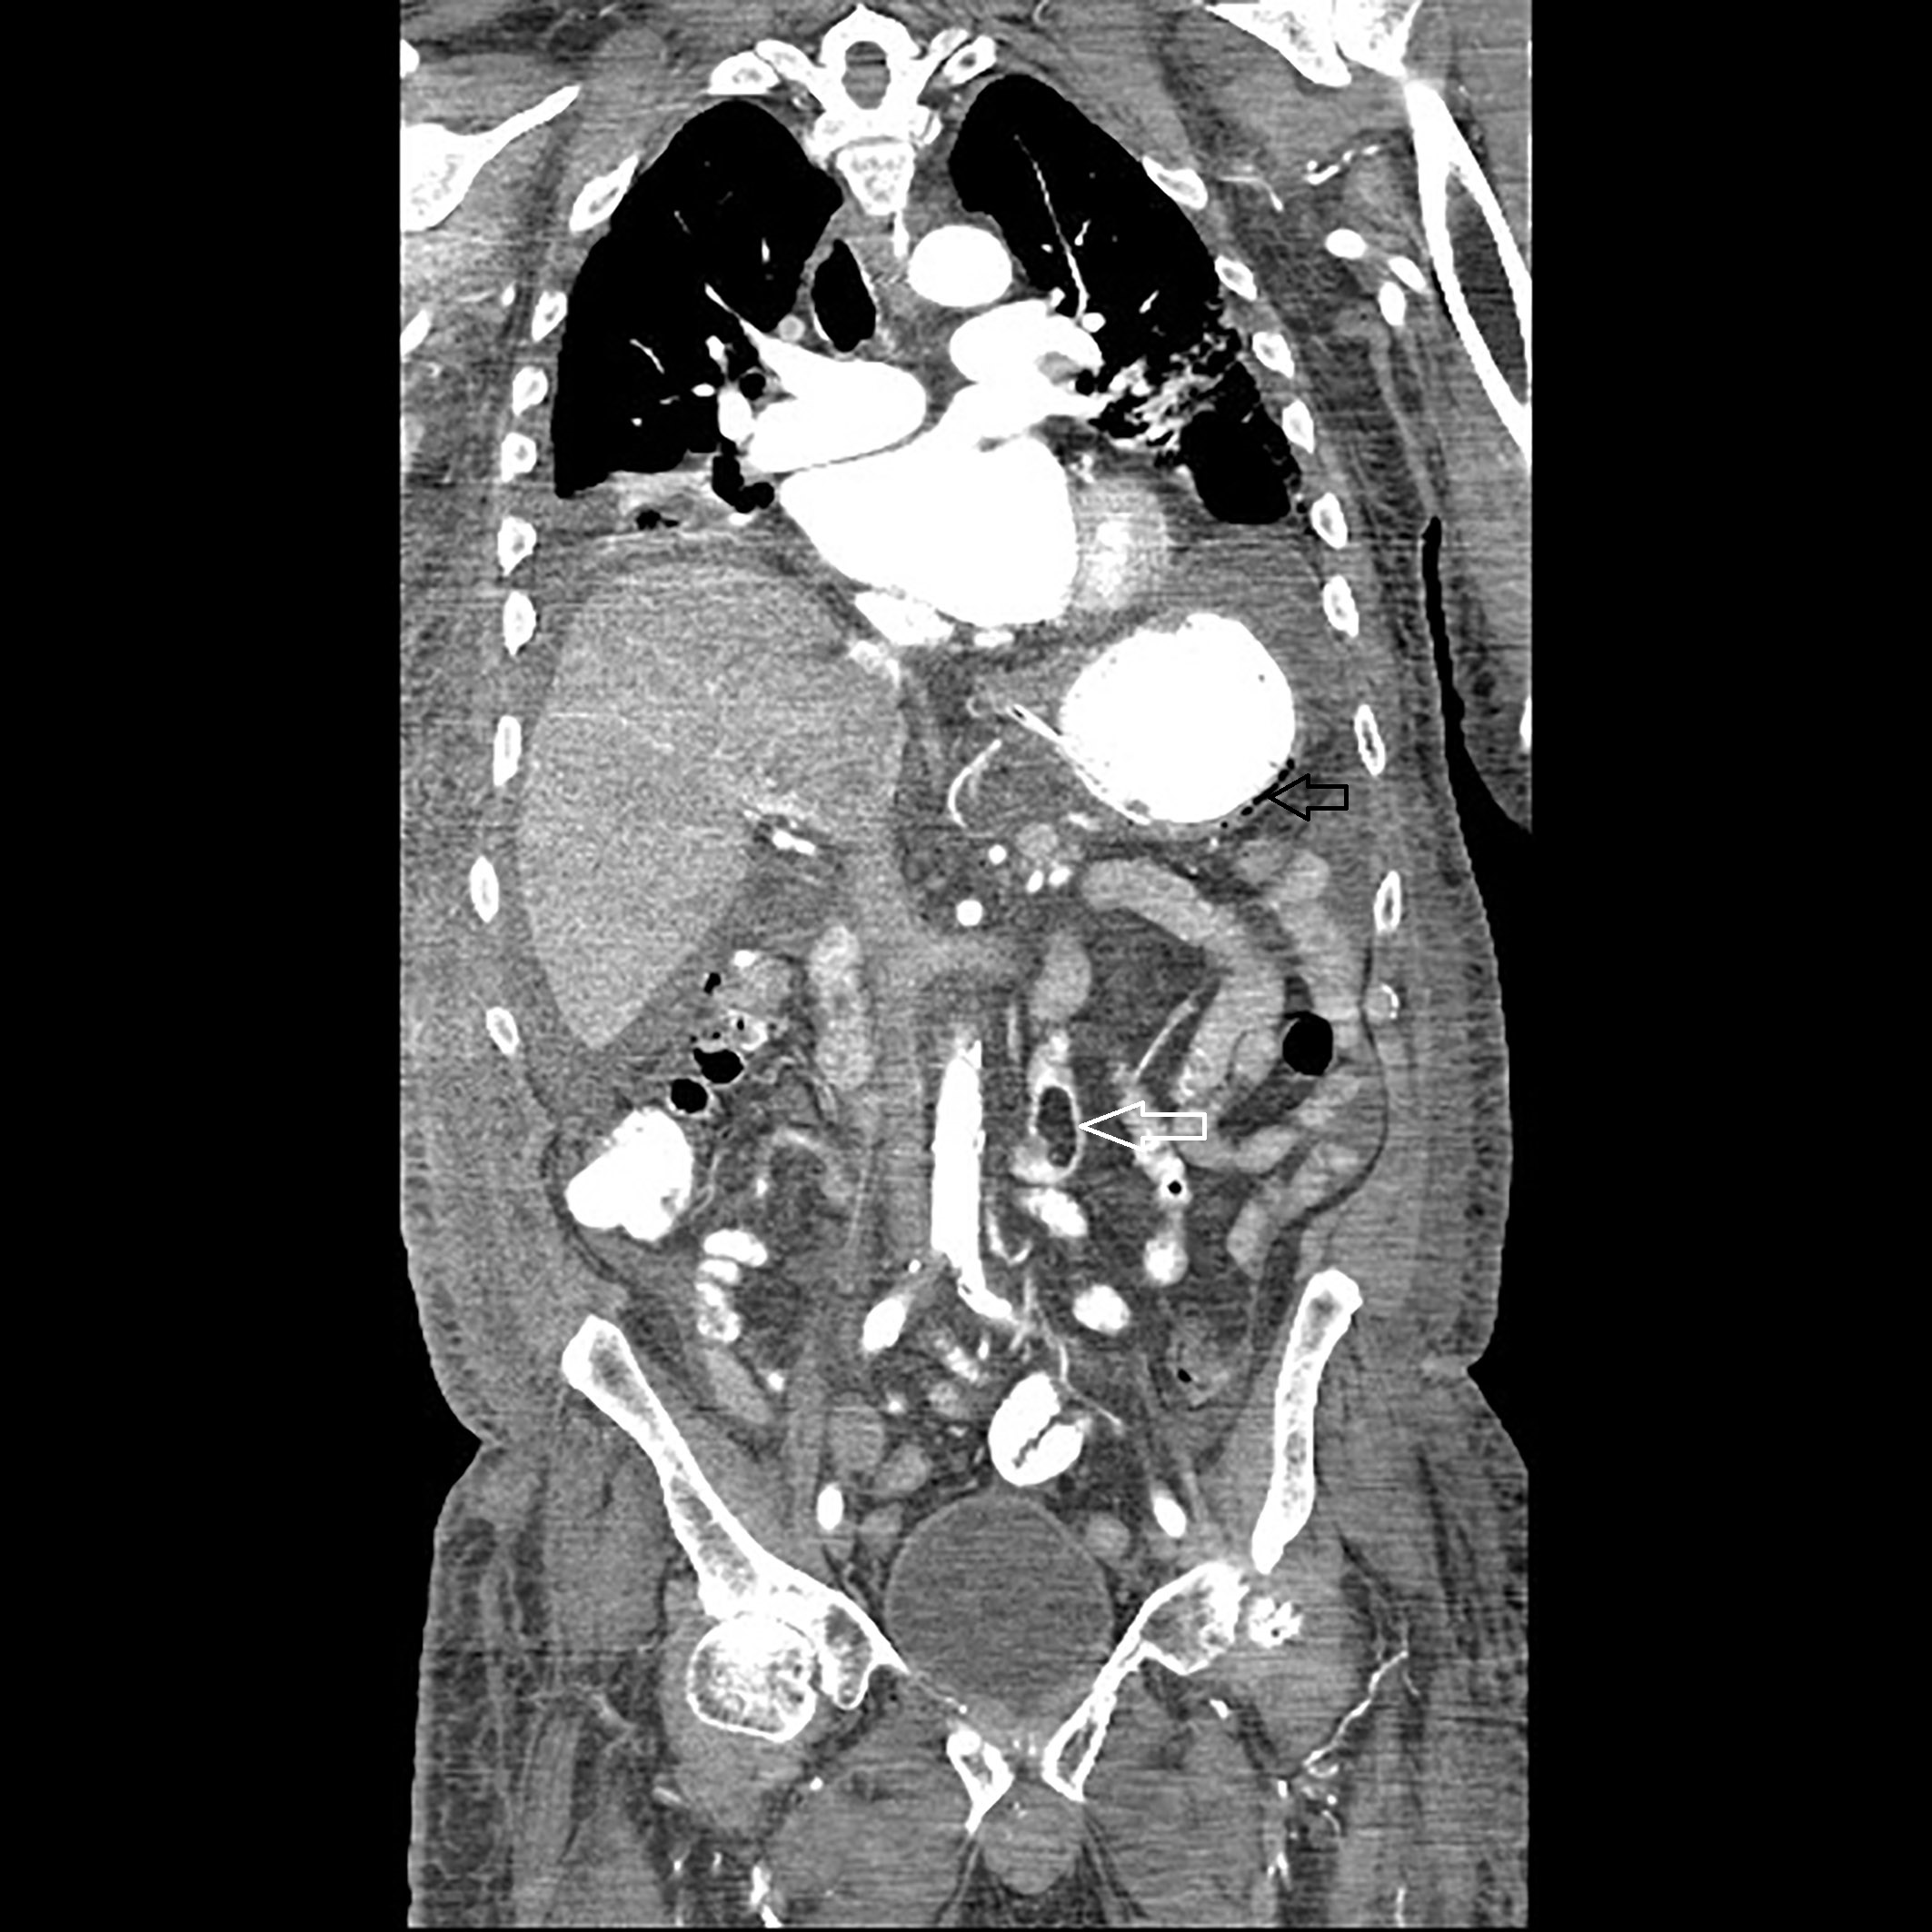

A 74-year- old nursing home resident male with CAD status post cardiac pacemaker, diabetic nephropathy current on hemodialysis and CVA without residual side-effects presented with fever of 102 F and altered mental status. Later he was admitted to the intensive care unit for acute respiratory failure, with bacteremia and septic shock most likely from right thigh abscess. On arrival, he was hypotensive and un-responsive to intravenous fluids. After rapid intubation and central line placement, he was started on aggressive hydration, intravenous vancomycin, pipercillin with tazobactam and pressors. White count 36.6 with left shift, metabolic acidosis on arterial gas with pH of 7.13 and lactic acid trending at 2.5 to 4.5 were noted. Later, a CT scan of right hip showed acute osteomyelitis involving the posterior aspect of the proximal to mid right femur with overlying abscess cavity. A CT scan (abdomen and pelvis) showed presence of gastric wall pneumatosis, transverse duodenal diverticulosis, 2.6cm small bowel lipoma and air/gas lucencies noted within the distal main and left portal veins (Figures 3 & 4). EGD showed mild gastritis in antrum of stomach and single smooth nodule measuring 5-6mm in size in the antrum (Figure 5). Owing to multiple co-morbidities, septic shock and unstable condition, conservative optimal management was made after the extensive family meeting. Later, the family opted for palliative care.

Figure 5 CT scan of the abdomen showing (a) presence of gastric wall pneumatosis (black arrow) and (b) 2.6 cm small bowel lipoma (white arrow).